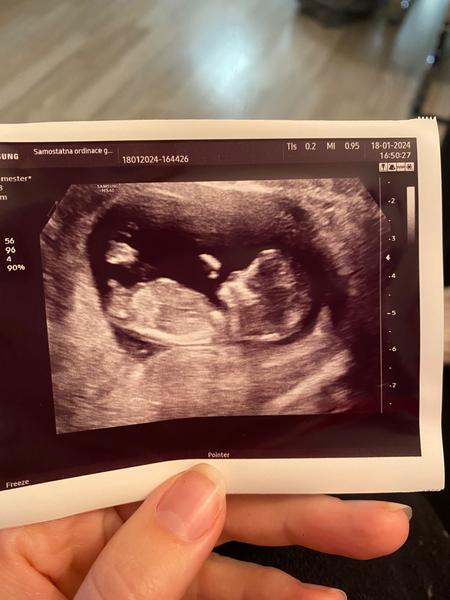

Teď u malé mi doktorka už na screeningu “naznačila” že by z toho holka mohla byt, v 17tt mi pak moje dr řekla 70-80% holčička a na druhem screeningu se ukázala sama a stále se mi potvrzuje ❤️